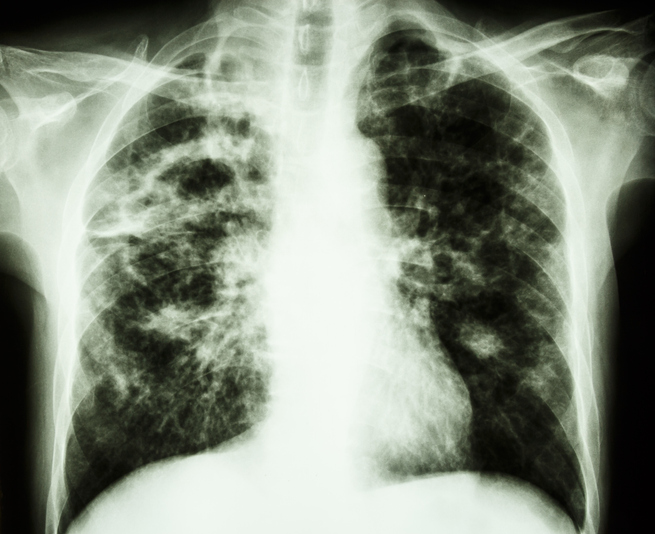

팔꿈치, 손가락, 치골, 아킬레스건 등에 나타나는 딱딱한 결절인 피하 결절이 생길 수 있습니다. 또한 관절의 염증 정도에 따라 빈혈이 잘 생길 수 있습니다. 심장, 폐, 눈, 신경, 간 등에서 전신 침범이 발생할 수 있는데, 이 경우에는 병의 경과 및 치료 결과가 좋지 않을 수 있습니다. 혈관염, 아밀로이드증, 폐섬유증이 여기에 해당됩니다.